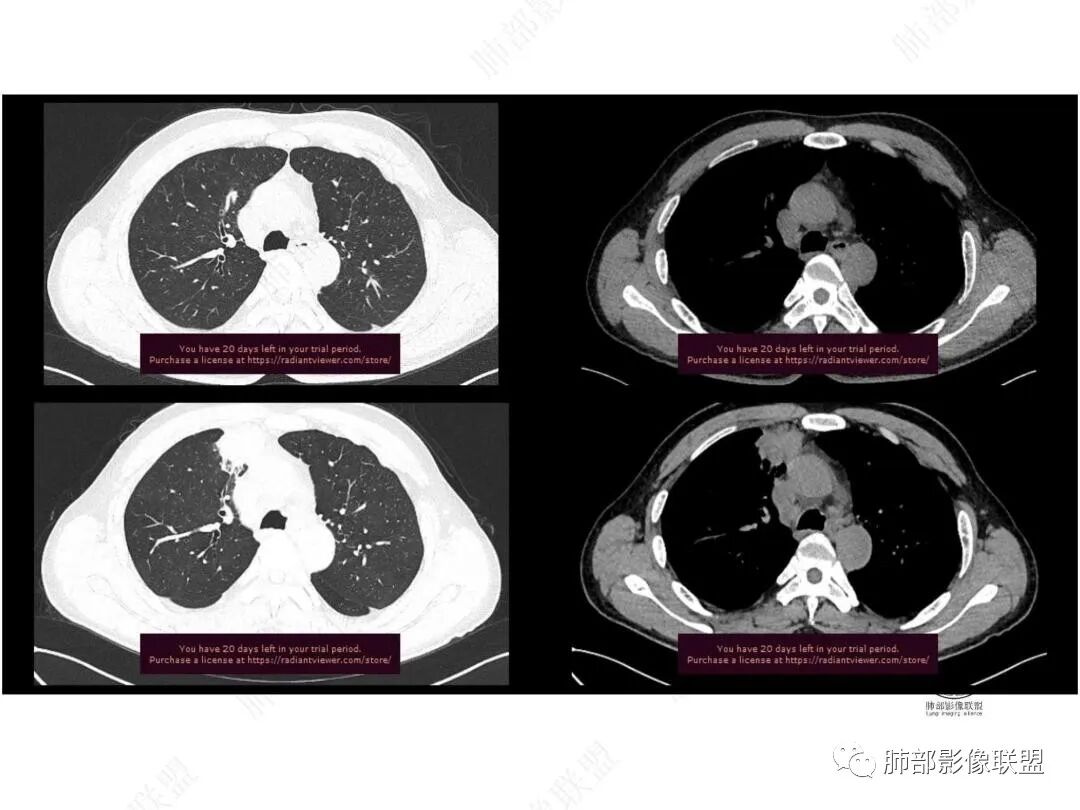

增强图像

中年男性,前纵膈旁团块,边缘平直,周围可见模糊的磨玻璃影,相邻支气管壁增厚,部分支气管进入病灶后阻塞,增强病灶渐进性强化,肝右叶见边缘不清的低密度影,增强渐进性强化。结合实验室检查,总体考虑炎性病变,自免性炎症?血管炎?

中年男性,右前纵隔旁不规则实变影,局部支气管进入后截断,病灶渐进性强化。肝脏右叶低密度灶,边界不清,呈明显渐进性强化。IMT?

中年男性,反复低热3月伴近期乏力及右上腹隐痛,白细胞,中性粒及淀粉样蛋白A增高,PCT不高,IGA、IGg增高,类风湿因子增高,未提供IGg4水平,影像改变,左侧肋骨陈旧性骨折(2020年已存在)右上叶前段胸骨旁的胸膜下新发病灶,支气管进入后一段才堵塞,肺动脉进入,走行自然,未见破坏,明显均匀强化,气管及支气管壁有增厚,钙化,纵隔内淋巴结增大,均匀强化,无坏死,纵隔内脂肪混浊,局部强化,肝内低密度灶,延迟强化(肺内病灶,淋巴结、混浊脂肪,肝内病灶强化均一致,且均为延迟强化)。初步考虑:免疫相关性炎症,IGg4相关炎症可能大,依据:IGA、IGg增高(未提供IGg4,可能是故意隐藏了),类风湿因子增高,炎性指标增高,但PCT不高,细菌感染可能就变小,加上病变同时累及肺、纵隔淋巴结,纵隔内脂肪、肝。

2.右肺上叶纵隔旁新发实性密度病灶,密度均匀,轻度强化,未见空洞、液化坏死及钙化,血管穿行自如,支气管进入后狭窄截止。灶周磨玻璃影边界不清,病灶未见明显分叶毛刺,平直、轻度收缩、周围偶见结节影,但未见树芽征。注意纵隔胸膜侵入或突入比较明确。纵隔淋巴结轻度增大。

3.右肺容易想到的病变有慢性炎症、IGg4相关、新生物(炎性肌纤维母细胞瘤、腺癌等)。但病灶侵入纵隔胸膜应当更符合恶性肿瘤。病程进展及强化等影像特点不支持继发性肺结核。

5.淋巴瘤可以解释影像改变,但仅凭影像及临床很难想到它是霍奇金!结外病变主攻方向以肝组织、肺组织为主,还突破胸膜?